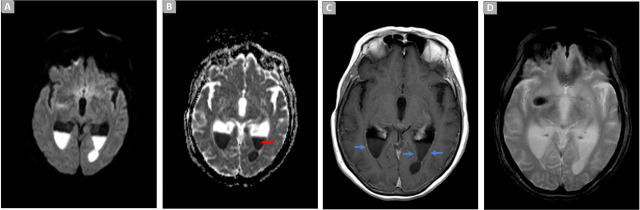

类风湿性关节炎是一种主要影响四肢小关节的炎症性风湿病,经常损害颈椎,导致脊柱不稳,可能需要进行手术治疗。这可能会导致严重的并发症,如脑室炎,通常与高死亡率和耐多药生物有关。如何在中枢神经系统中达到治疗性抗菌浓度是一大挑战。作者介绍了一例 65 岁女性因严重类风湿性关节炎导致颈椎脊髓病变的病例。手术后,患者出现了由广泛耐药的绿脓杆菌引起的脑室炎。早期诊断和及时治疗在促进神经和认知康复方面发挥了至关重要的作用。

Rheumatoid arthritis, an inflammatory rheumatic disease predominantly affecting small limb joints, frequently compromises the cervical spine, resulting in spinal instability and the potential surgical necessity. This may result in severe complications, such as ventriculitis, often associated with a high mortality rate and multidrug-resistant organisms. A major challenge lies in achieving therapeutic antimicrobial concentrations in the central nervous system. The authors present a case of a 65-year-old female, with cervical myelopathy due to severe rheumatoid arthritis. Following surgery, the patient developed ventriculitis caused by an extensively drug-resistant Pseudomonas Aeruginosa. Early diagnosis and prompt treatment played a crucial role in facilitating neurological and cognitive recovery.